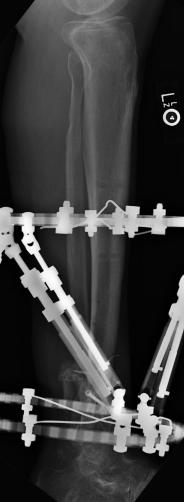

Pre-corrective surgery X-Rays of the damaged right & left legs / ankles

These x-rays were taken at Dr Armendariz’s office, just prior to performing any corrective surgery. As can be seen in these images,

there was no tibia bracing provided by Dr. Keller. Liam was released from Dr Keller’s care with instructions that full weight bearing could

be accomplished within 2 months of Keller’s last surgical procedure. The best example to examine is the second image (from the left) of the

top how. Notice how the bones that should be aligned with the tibia are in fact on the other side of the leg. The third image shows how badly

Liam’s left foot was twisted as a result of the pool placement of the external fixation. What is not obvious is that the screw at the bottom

of the plate on the right fibula missed being screwed into the plate.